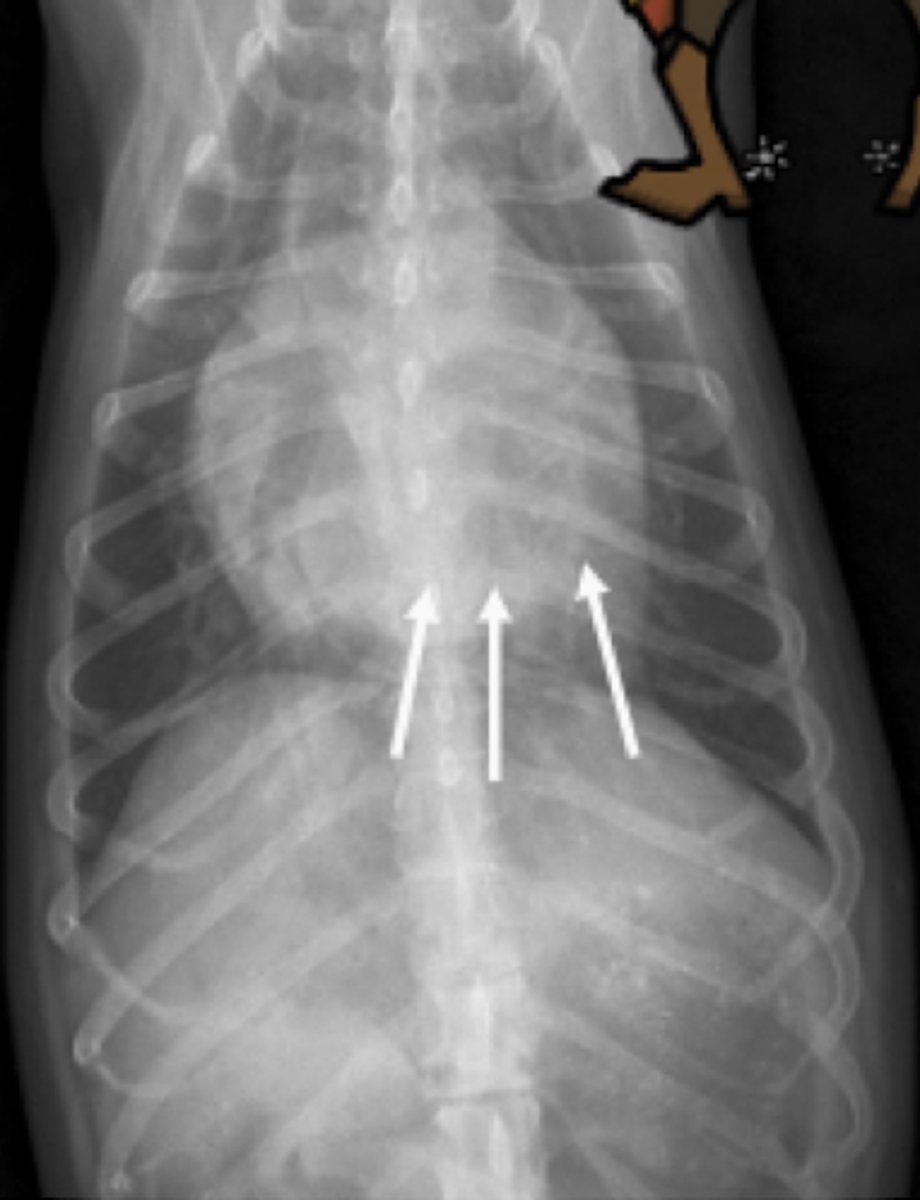

efusión pleural

patología:

efusión abdominal